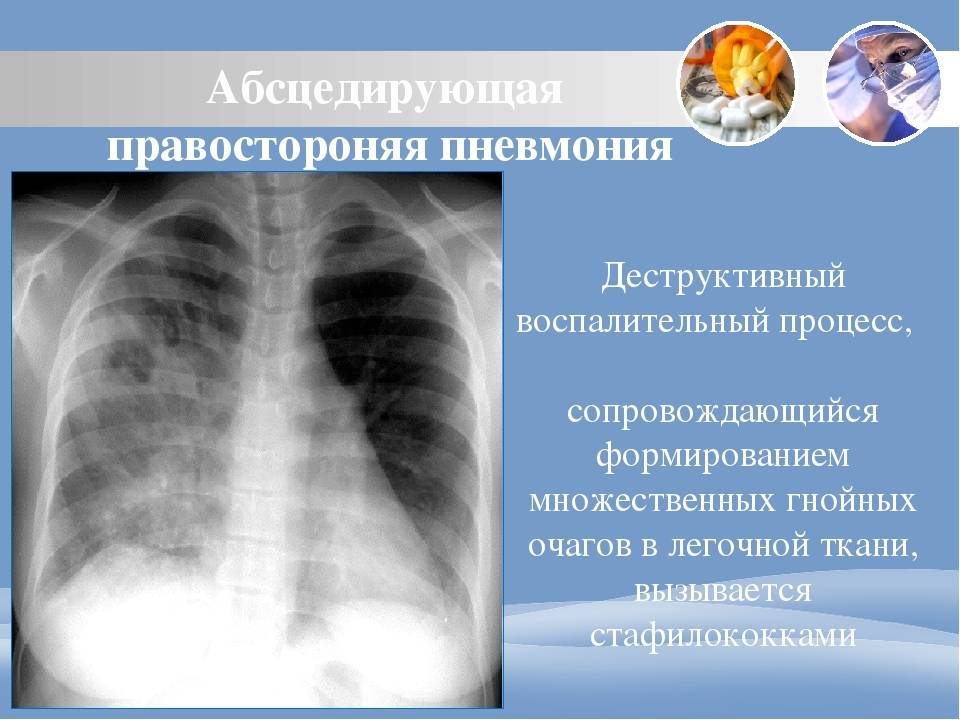

Бактериальная деструкция легких у детей презентация - 88 фото